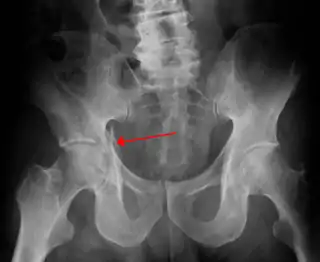

Fractura de acetábulo

La fractura de acetábulo o fractura de cavidad cotiloidea, es un tipo de fractura ósea que afecta a la cavidad cotiloidea en la pelvis. No debe confundirse con la fractura de fémur, en la fractura de acetábulo el fémur permanece indemne, salvo que exista lesión combinada.[1]

![]() Radiografía en la que puede visualizarse una fractura de acetábulo | ||